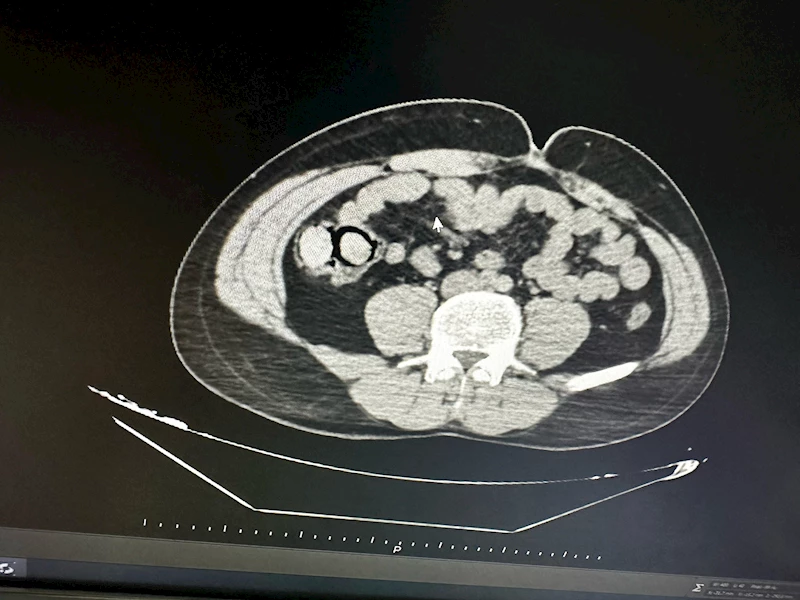

Aziz ÖNAL/ BİNGÖL, (DHA)- BİNGÖL’de polis ekiplerince düzenlenen uyuşturucu operasyonunda midelerinde 10 parça halinde 113 gram metamfetamin tespit edilen 2 şüpheli, tutuklandı.

İl Emniyet Müdürlüğü Narkotik Suçlarla Mücadele Şube Müdürlüğü ekipleri tarafından gerçekleştirilen operasyonda, uyuşturucu ticareti yapmak üzere kente otobüsle geldiği bilgisine ulaşılan 2 şüpheli gözaltına alındı. Şüphelilerin hastanede yapılan muayenelerinde, midelerinde toplamda 10 parça halinde 113 gram metamfetamin maddesi ele geçirildi. Şüphelilerin midelerindeki uyuşturucu paketleri, hastanede yapılan işlemle çıkarıldı. Emniyetteki işlemlerinin ardından adliyeye sevk edilen şüpheliler, sevk edildikleri adliyede çıkarıldıkları mahkemece tutuklanarak cezaevine gönderildi.(DHA)